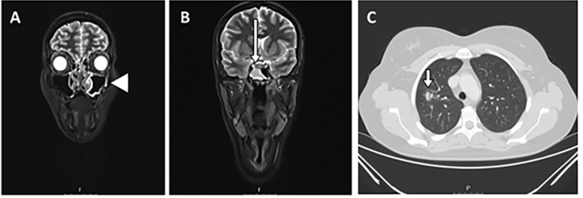

The authors present a case of a 30-year-old woman who use to work as a lyric singer, with a history of chronic otorrhea and recurrent otalgia associated with chronic nasal obstruction, relapsing epistaxis and headaches. Ear examination showed a double perforation on the left tympanic membrane and the nasopharyngolaryngoscopic examination showed bilateral ulceration and crusting of the nasal mucosa, without any laryngeal findings. Nasal and pulmonary biopsies showed a granulomatous and necrotic inflammatory process, compatible with granulomatosis with polyangiitis (GPA). Anti-neutrophil cytoplasmic antibody (ANCA) levels were elevated. Imaging study revealed bilateral chronic rhinosinusitis and a pulmonary nodule (Figure 1). She was then treated with prednisolone and azathioprine. A year later, after the negativity of ANCA levels, systemic improvement and initiation of immunosuppressors withdrawal, she was admitted to the emergency department with dyspnea and stridor, requiring an emergent tracheostomy. At that time, the laryngological examination showed a severe subglottic stenosis with a maximum diameter of 4mm (Figure 2A). One week later, she underwent elective surgical repair of the subglottic defect with laser, balloon dilation, and mitomycin and prednisolone local application. First, endoluminal laser star incisions were performed so we can enlarge the airway lumen (Figure 2B). Next, we proceed to local infiltration of prednisolone and application of mitomycin C followed by dilation with an 11mm balloon and hemostasis (Figure 2C). After 2 years of follow-up, there are no signs of tracheal stenosis. She started singing again.

Figure 1 Imaging study with maxillo-facial and neck magnetic resonance imaging (MRI) revealed signs of chronic rhinosinusitis with bilateral inflammatory mucosal thickening of ethmoid, maxillary and sphenoid sinuses (arrowhead), particularly in the right sphenoid sinus (long arrow) (A, B). MRI of the lung showed the presence of an irregular nodule in the right superior lobe (17mm) and another adjacent regular nodule with 11 mm (C, short arrow).